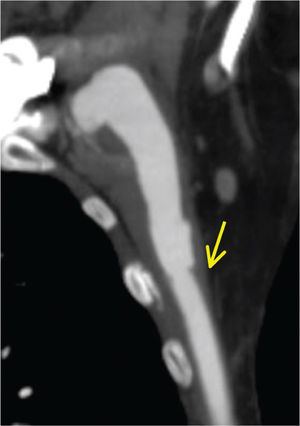

Objectivamente apresentava volumosa massa pulsátil e expansível indolor infra-clavicular esquerda, com enxerto pulsátil e pulsos distais presentes no membro inferior esquerdo. A avaliação por «Triplex Scan» e angioTC mostraram disrupção completa da anastomose axilar e migração distal da prótese axilo-femoral permeável (figs. 1 e 2).